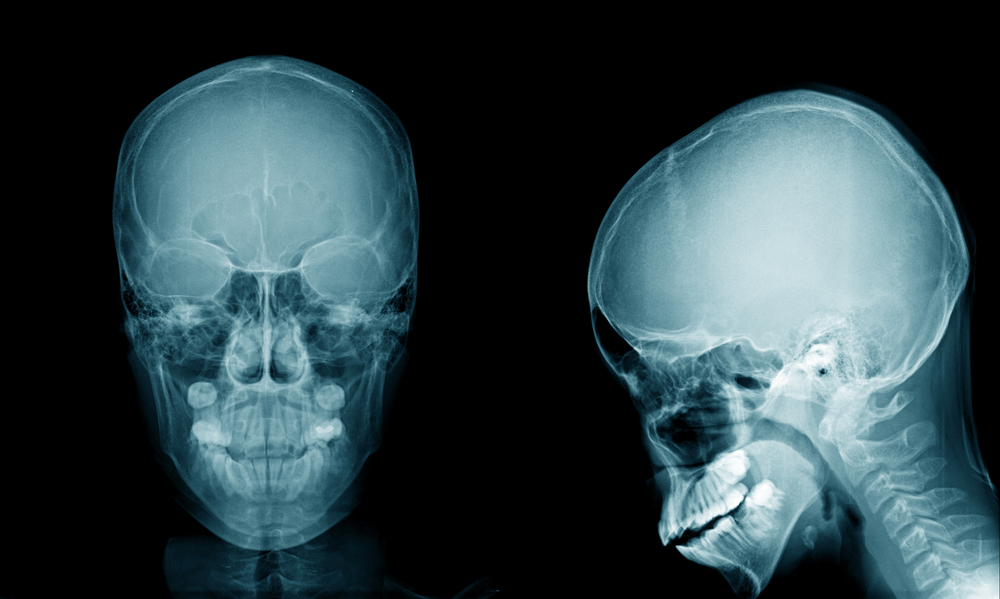

Базилярная импрессия: причины, симптомы и лечение

Базилярная импрессия (базилярная инвагинация) – это патологическое состояние, заключающееся в смещении в полость черепа краев затылочного отверстия, затылочных мыщелков и зубовидного отростка второго шейного...